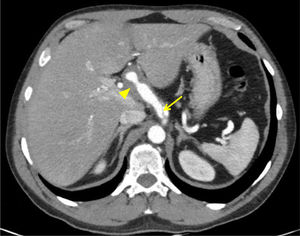

Therefore, a computed tomography (CT) scan of the chest, abdomen and pelvis was performed to conduct a detailed investigation of the ultrasound findings and complete the extension study. This found an “intimal flap” suggestive of coeliac trunk dissection extending to the hepatic artery with pseudoaneurysm of that artery, as well as dissection of the middle third of the superior mesenteric artery, with no aortic involvement (Fig. 1). No abnormalities were seen in the liver or in the biliopancreatic area.